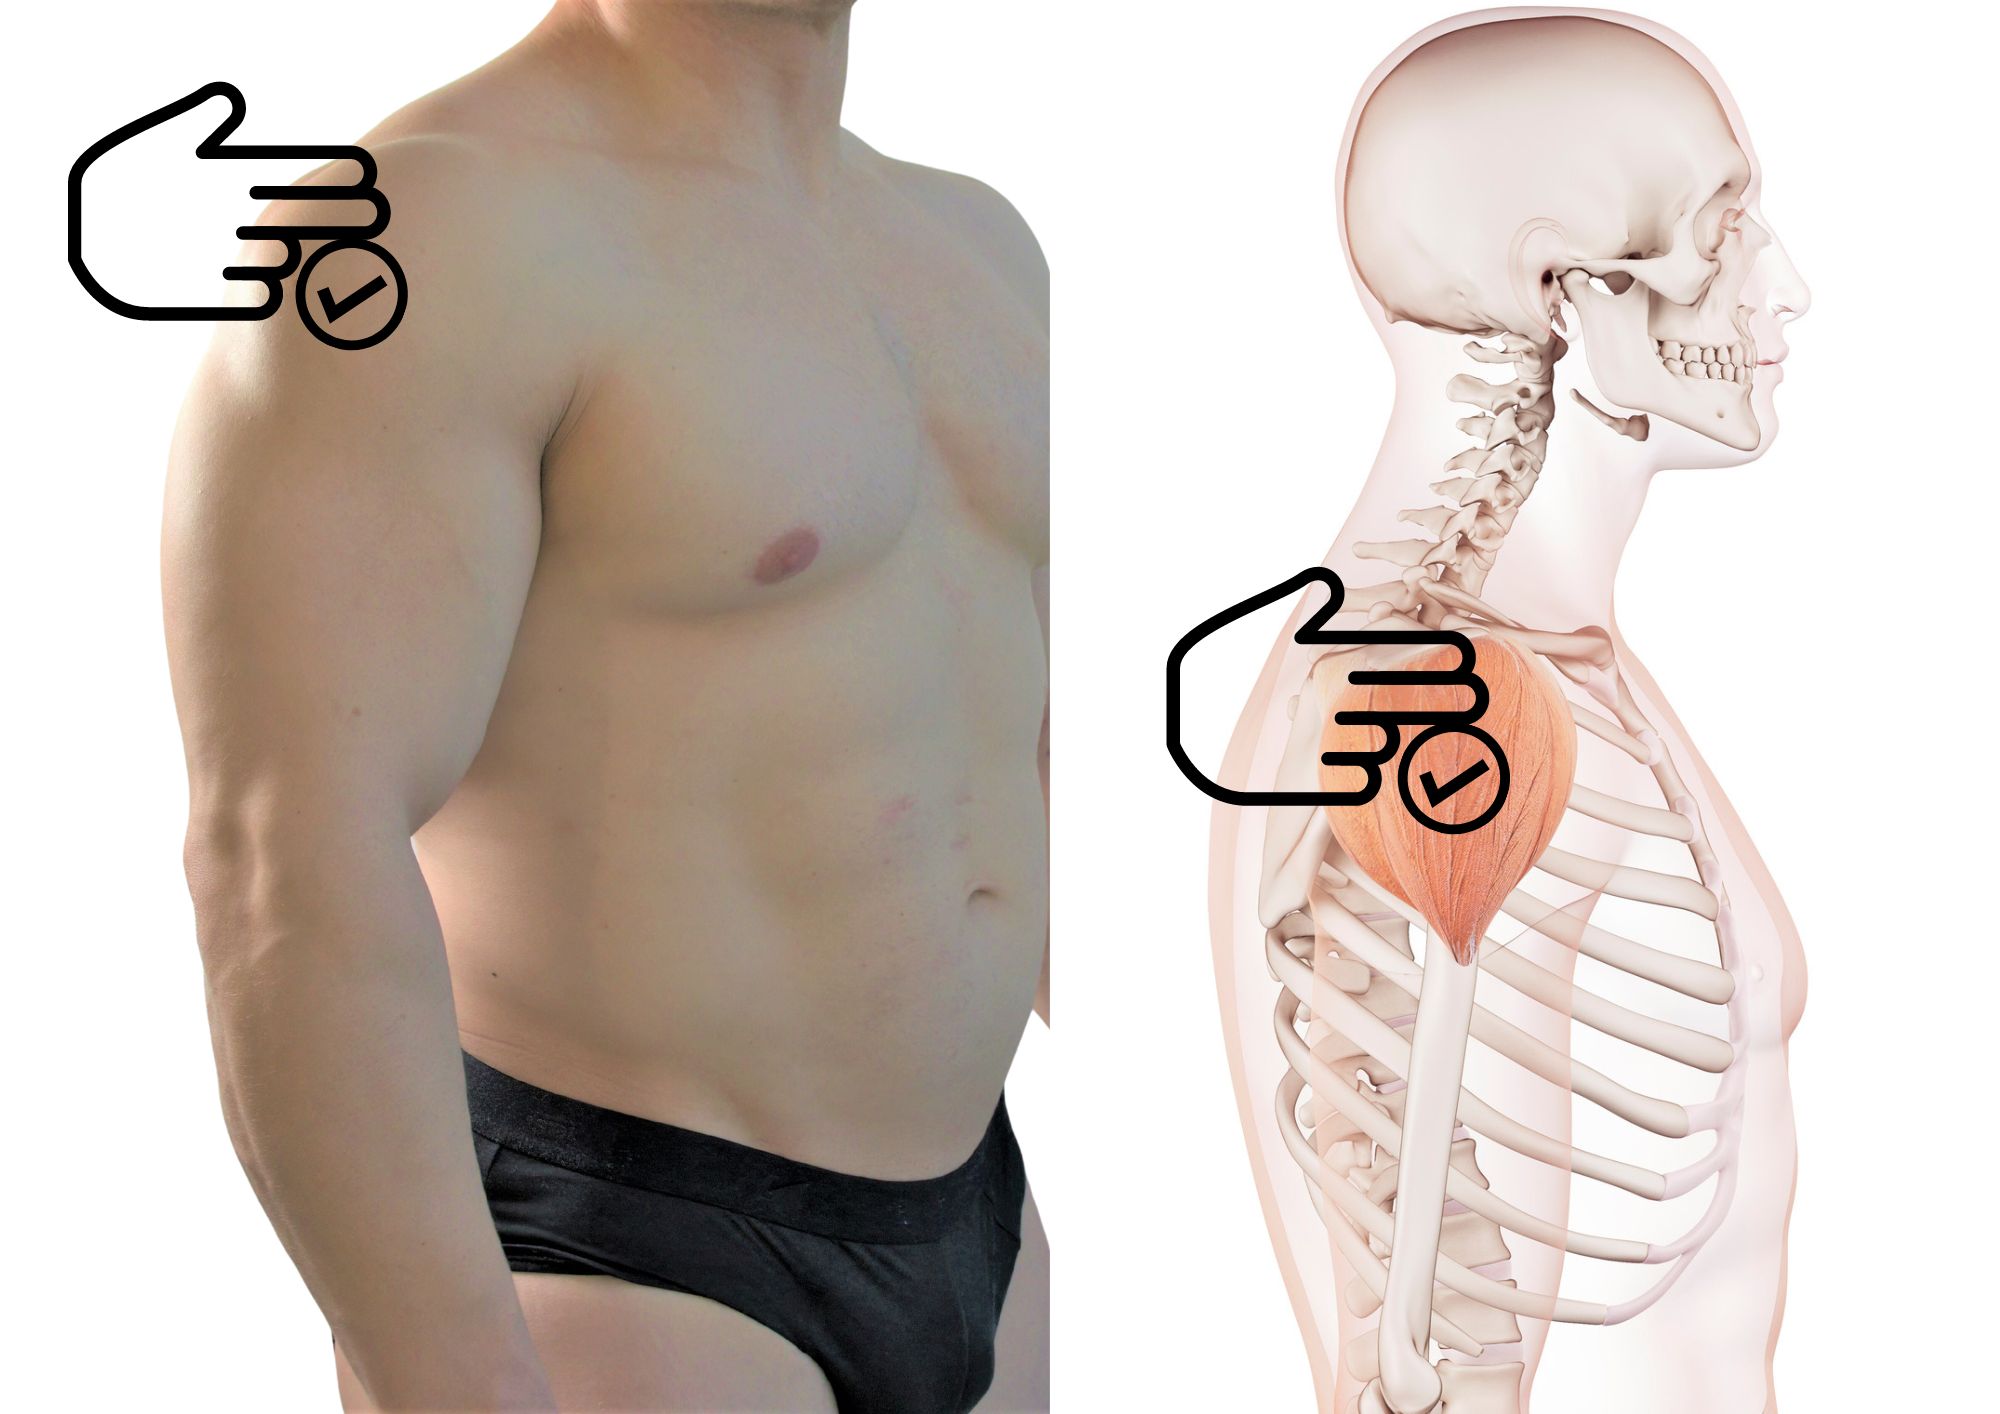

Фотографии поддельтовидной мышцы плечевого сустава

Раздел: Образы вокруг